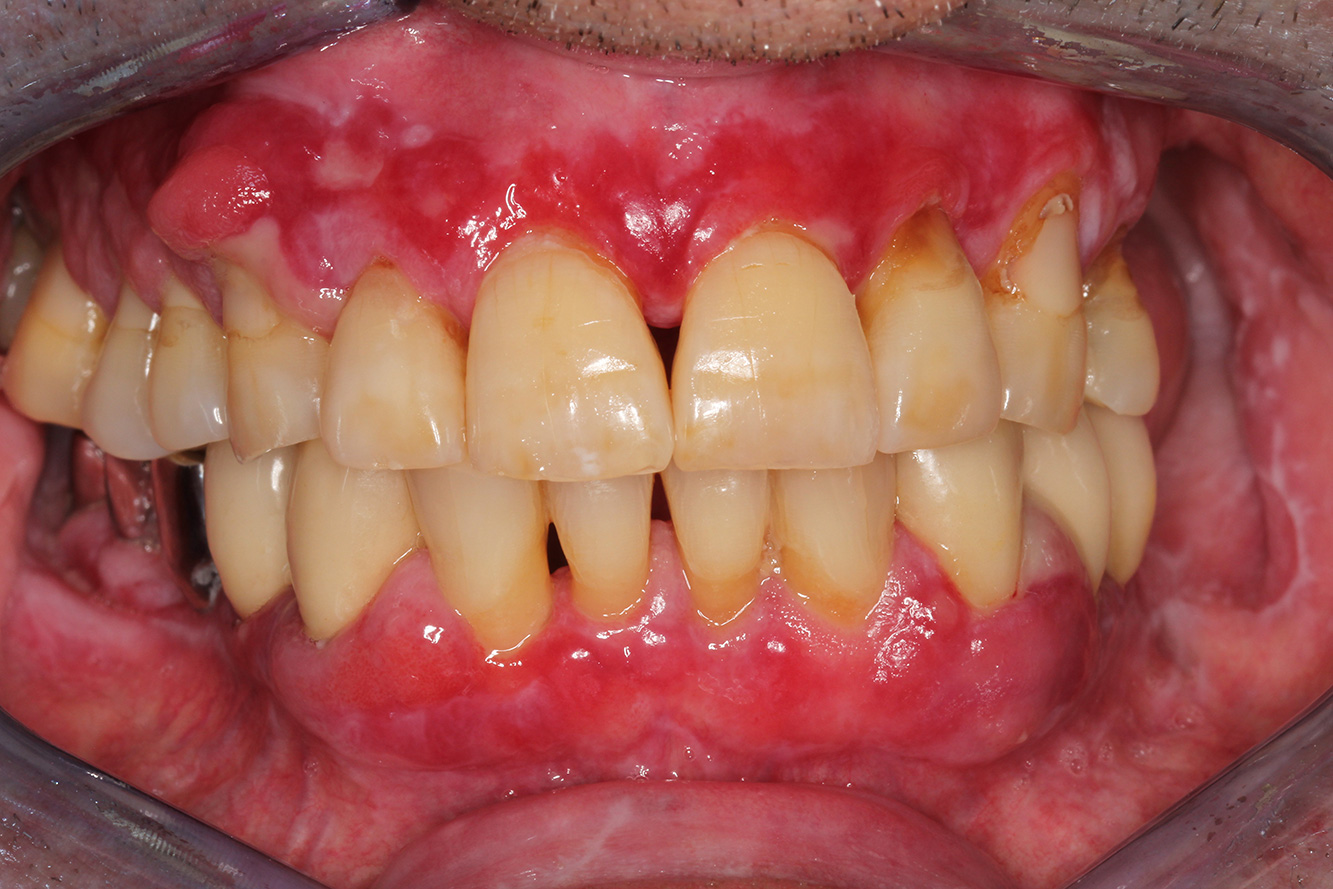

Der Diabetiker mit Parodontitis

Dieser Fallbericht eines 52-jährigen Mannes mit Typ-2-Diabetes und Parodontitis hebt hervor, wie durch individuelle Vorsorgemaßnahmen, die Gesundheit des Zahnhalteapparates erhalten bzw. das Fortschreiten der Erkrankung kontrolliert werden kann. mehr Infos